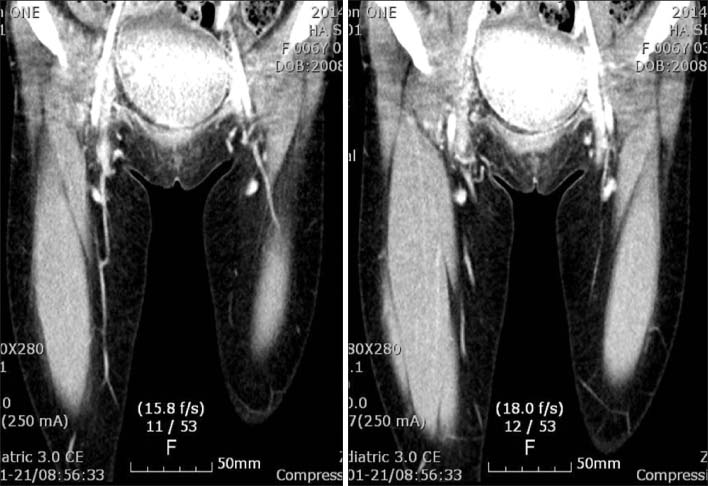

Fig. 4

CT showed a small lobulating contoured fatty mass like lesion in right inguinal area and nonenhancing right common femoral and external iliac vein with collateral.

Fig. 4 CT showed a small lobulating contoured fatty mass like lesion in right inguinal area and nonenhancing right common femoral and external iliac vein with collateral.